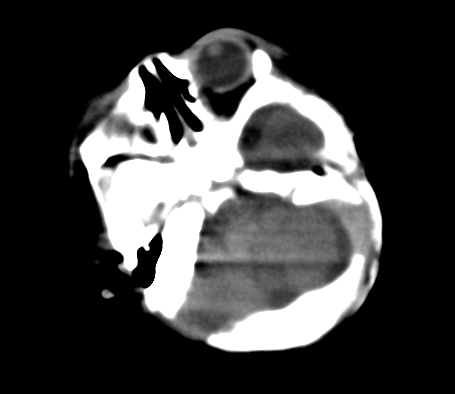

患儿,出生时正常,第5天突然呕吐两次,无发热及抽搐。

片示:双侧大脑半球脑实质密度降低,皮髓分界尚清,左侧顶部脑沟内见铸形高密度影,脑中线结构居中。

2、hie并少量蛛网膜下腔出血。